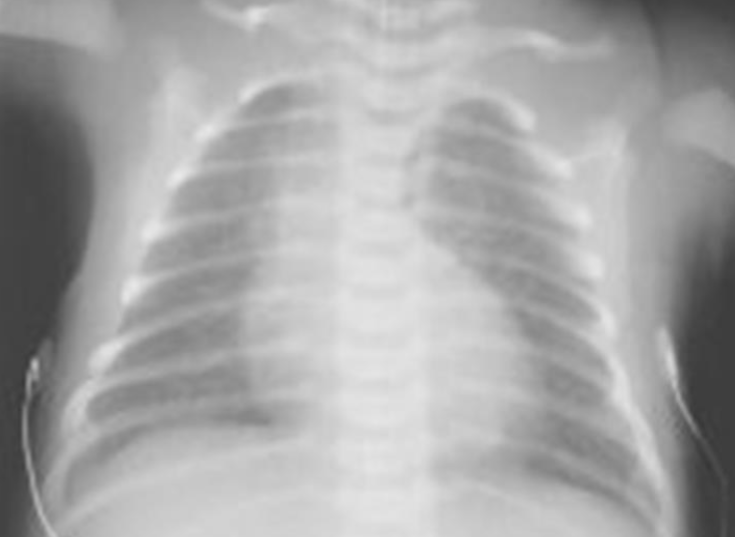

Case: Preterm Infant with Respiratory Distress

- Preterm 29 weeks gestation C/S delivery showed severe respiratory distress soon after birth - RDS

- Air bronchograms

There is a homogeneous opacification of both lungs with white-out lungs - (1 .field (grounds glass appearance) and air bronchogram bilaterally

.The diagnosis is Acute Respiratory Distress Syndrome (ARDS) - (2

- .I- Massive blood transfusions Preterm 29-weeks gestation C/S delivery showed severe respiratory distress soon after birth. This chest x-ray was taken at the age of 6 hours.

- Q1: Write 2 abnormalities in the X-Ray?

- Q2: What is the likely diagnosis?

- Q1: Ground glass appearance, wide intercostal space.

- Q3: Mechanical ventilation, give Surfactant for lungs maturation.